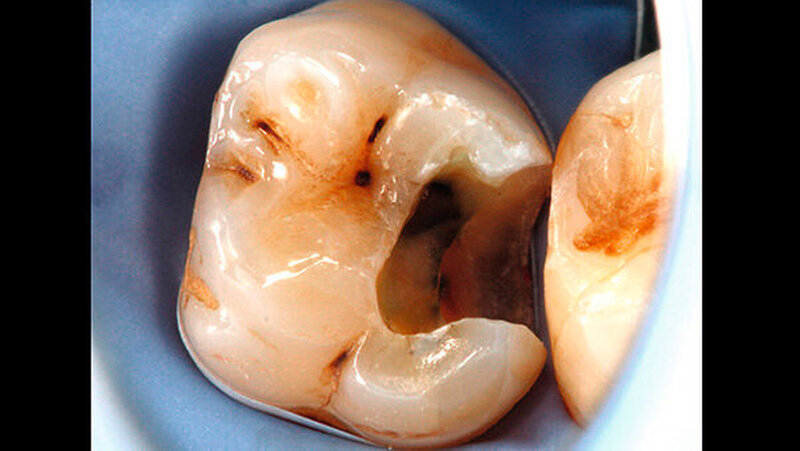

Ein 72-jähriger Patient stellte sich im Oktober 2013 zu einer Routinekontrolle in der Poliklinik für Zahnerhaltung und Parodontologie der Universität Regensburg vor. Bei der Befunderhebung wurde aufgrund des Verdachts auf Approximalkaries eine Röntgenaufnahme im Bereich des zweiten Quadranten angefertigt. Im Bereich des Zahns 26 distal wurde eine "Caries profunda“ diagnostiziert (Abbildung 1) und daher ein Termin zur Füllungstherapie vereinbart.